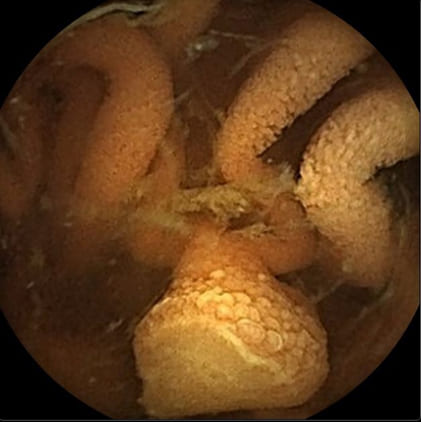

tomography (PET) scan revealed an increased uptake in the ileal tract (Standardized Uptake Value 12). Subsequently, we decided to perform VCE which showed deep black partially confluent ulcers surrounded by whitish area, indicative of haemorrhagic melanoma metastasis (Figure 2), and 5 further blue and non-pigmented sessile and pedunculated polypoid (Figure 3) lesions in the jejunum as well as a Merkel diverticulum in the ileum.

Figure 2: VCE appearance of small bowel melanoma metastasis